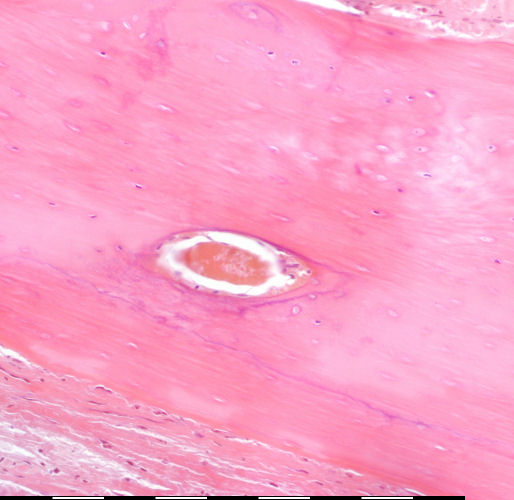

Medium magnification of immature bone

Osteosiete / Osteocytes Endosteale selle / Endosteal cells Groeilyne / Growth reversal lines